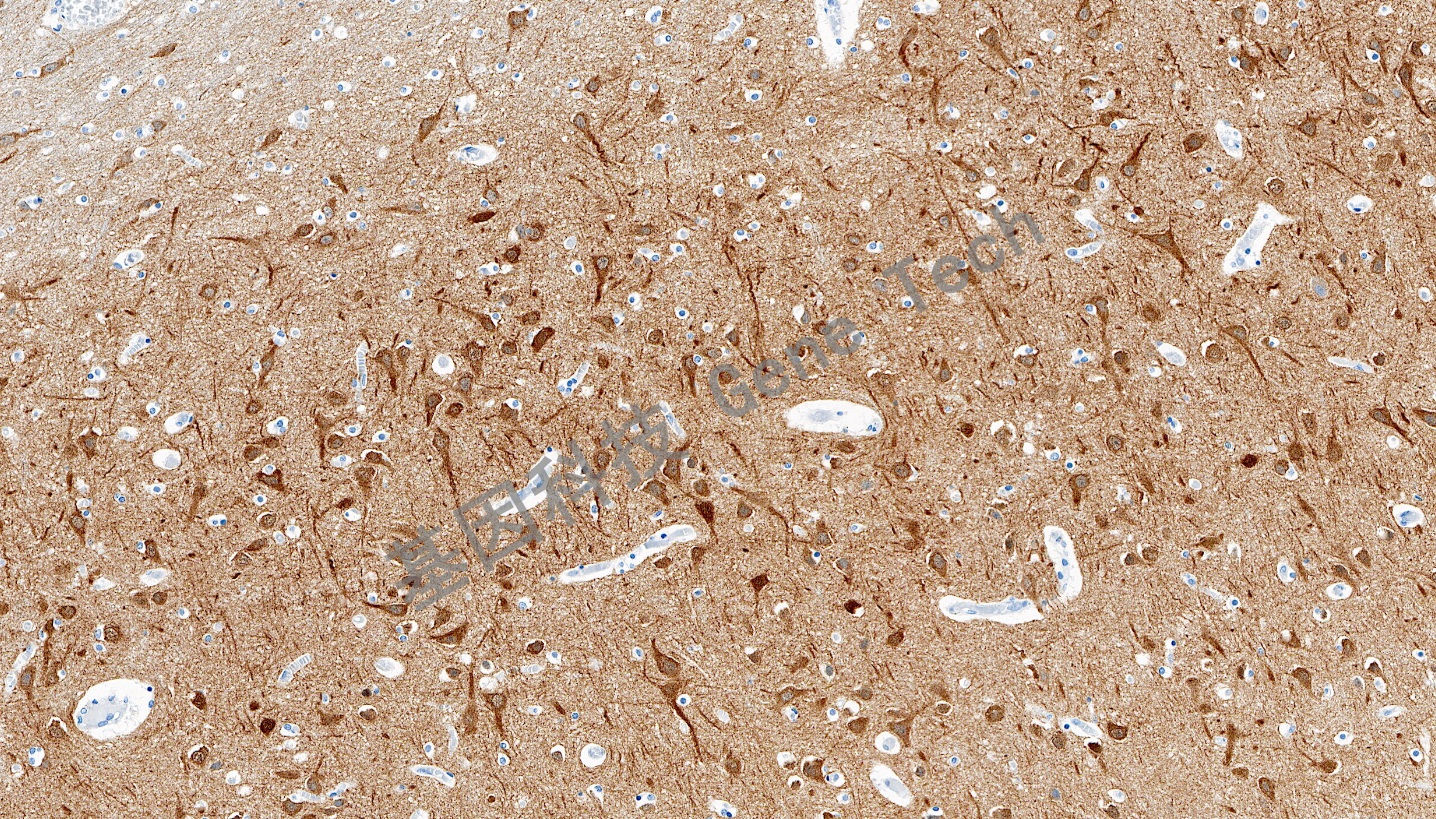

DCLK1 兔抗人 雙腎上腺皮質(zhì)激素樣激酶1(DCLK1) 抗體試劑(免疫組織化學(xué)法)

| 預(yù)處理:高pH熱修復(fù) | 陽性部位:細胞膜/細胞漿 | 陽性對照:腦 |

| 腦石蠟切片,用 DCLK1(GT2565)染色,細胞膜/細胞漿陽性,DAB 顯色。 | ||